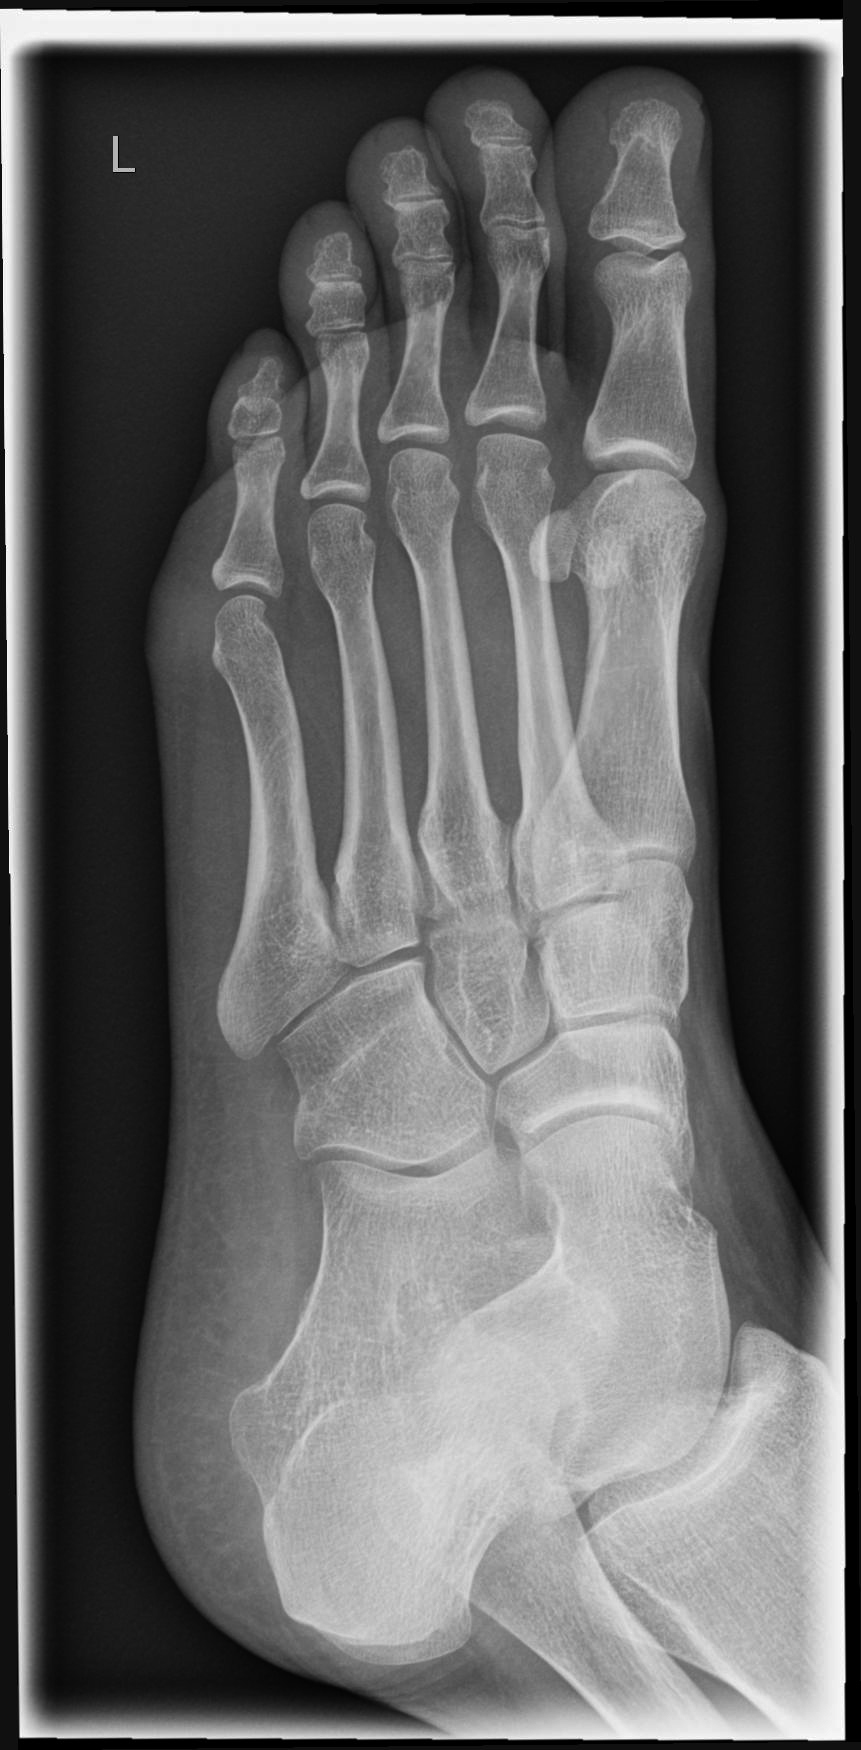

Fuß dorso-plantar (a.-p.) unter Belastung

Technik

• FDA: 1,05 m

• Ausgangsformat: 24/30

• Röhrenkippung

• Übertischaufnahme

Lagerung

stehend auf Bildempfänger

Knie leicht gebeugt und zweiten Fuß nach hinten versetzen um das Gleichgewicht zu halten

Es soll eine Belastung auf den Fuß erfolgen, aber nicht so, dass das Knie und die Bleischürze genau über dem Fuß schweben.

Zentralstrahl

Leicht Kippung zum Patienten auf Objektmitte

Einblendung

proximal bis einschließlich Malleolus lateralis

Anmerkung

Häufig passiert es, dass der Patient mit seinem Knie zu sehr über den Fußrücken kommt bzw. ins Lichtvisier. Deshalb mit dem zweiten Fuß einen leichten Schritt nach hinten machen und kontrollieren, dass das Knie und die Bleischürze nicht über dem Fuß schwebt.

Qualitätskriterien

Vollständige überlagerungsfreie Darstellung des ganzen Fußes a.p.